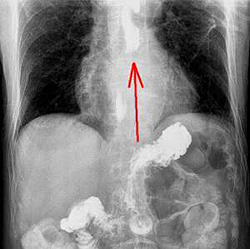

Стриктура пищевода после химического ожога

в) Диагностика. Диагноз устанавливают на основании типичного анамнеза (случайное или преднамеренное (с целью суицида) употребление едкого вещества) и характерных местных признаков. Следует выяснить природу едкого вещества, выполнить рентгенографию грудной клетки и живота. Если по данным анамнеза и клинического обследования ожог не тяжелый, то выполняют контрастное рентгенологическое исследование пищевода, после чего осторожно исследуют пищевод и желудок эндоскопом и вводят желудочный зонд.

Первую эзофагоскопию с соблюдением необходимых предосторожностей выполняют через 6-8 дней. Если при рентгенологическом исследовании и эзофагоскопии выявляют стеноз пищевода, то с конца 2-й недели начинают дилатацию пищевода. В дальнейшем эзофагоскопию выполняют каждые 10 дней, пока дефекты слизистой оболочки не эпителизируют. После этого контрольную рентгенографию и эзофагоскопию выполняют через 1, 3, 6 и 12 мес.

Начинают с подбора бужа подходящего размера с помощью эзофагоскопии. Предварительно с помощью контрастной рентгеноскопии уточняют локализацию стеноза и исключают злокачественную опухоль и множественные стенозы.

После стабилизации общего состояния возможно проведение рентгенографии пищевода. В острой фазе ожога на рентгенограмме отмечается утолщение складок слизистой оболочки, данные за гиперкинезию пищевода. Консультация врача-эндоскописта в остром периоде более информативна: во время эзофагогастроскопии визуализируется гиперемия и отек эпителия, изъязвления и эрозии пищевода, налеты. В подострой фазе рентгенография пищевода выявляет стриктуры, расширение пищевода над стенозированным участком, умеренный эзофагит. Эндоскопическое исследование в подостром периоде позволяет обнаружить некротический струп, определить границы поражения, визуализировать грануляции и формирующиеся рубцы. В хронической стадии процесса можно выявить разнообразные виды рубцовых изменений: клапанные, в виде колец, трубчатые и др. Изредка рубцы пищевода могут малигнизироваться.